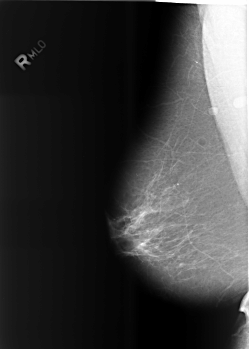

Digital Database for Screening Mammography

Volume: benign_13 Case: B-3466-1

B_3466_1.RIGHT_MLO

RIGHT_MLO LINES 5576 PIXELS_PER_LINE 3984 BITS_PER_PIXEL 12 RESOLUTION 50 NON_OVERLAY

FILE: B_3466_1.LEFT_MLO.OVERLAY

TOTAL_ABNORMALITIES 3

ABNORMALITY 1

LESION_TYPE CALCIFICATION TYPE FINE_LINEAR_BRANCHING DISTRIBUTION CLUSTERED-LINEAR

ASSESSMENT 4

SUBTLETY 2

PATHOLOGY BENIGN

ABNORMALITY 2

LESION_TYPE CALCIFICATION TYPE PLEOMORPHIC DISTRIBUTION CLUSTERED

SUBTLETY 4

ABNORMALITY 3

LESION_TYPE MASS SHAPE LYMPH_NODE MARGINS CIRCUMSCRIBED

ASSESSMENT 0

SUBTLETY 5

PATHOLOGY UNPROVEN